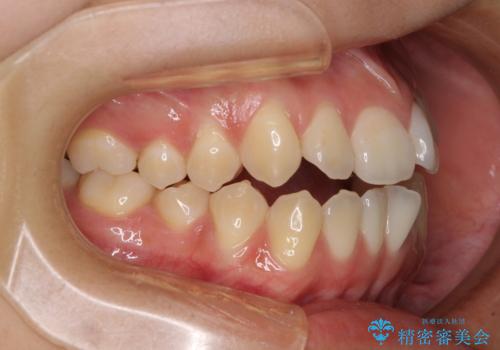

受け口と開咬を急速拡大装置とワイヤー装置で改善

- 前歯の開咬と、受け口による咬み合わせの悪さを気にして来院された患者様です。

上顎歯列が狭窄していたため、急速拡大装置により上顎骨を側方に拡大し、その後ワイヤー装置にて矯正治療を行うこととしました。